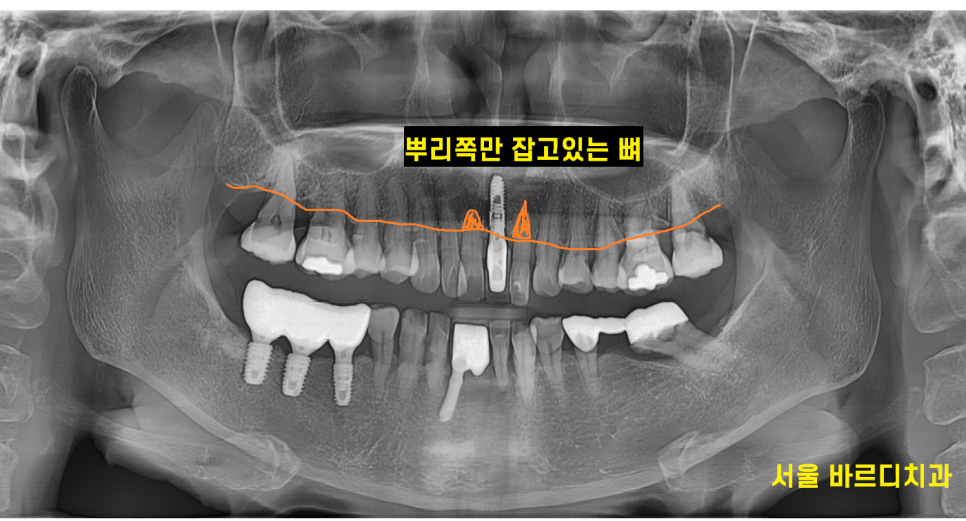

잇몸 뼈 확인을 위하여 x-ray를 찍어보니

역시나 치아를 붙잡고 있는 잇몸뼈가 없습니다.

이러니 윗니 앞니 흔들림이 발생하죠.

230826

ct 사진을 분석해보니

빨간색 동그라미 부분을 봐주세요.

까만 부분이 보이시죠?

이 부분이 뼈가 녹은 부위인데

한쪽 벽면이 다 녹았습니다.

윗니 앞니 흔들림 증상 외에도

뼈가 치아를 붙잡아주지 못해

치아가 자꾸 내려오고

뻐드러져 보이는 현상 발생

문제 해결을 위해서는 최소 2개 치아는 뽑아야

불편감을 해소해드릴 수 있었습니다.